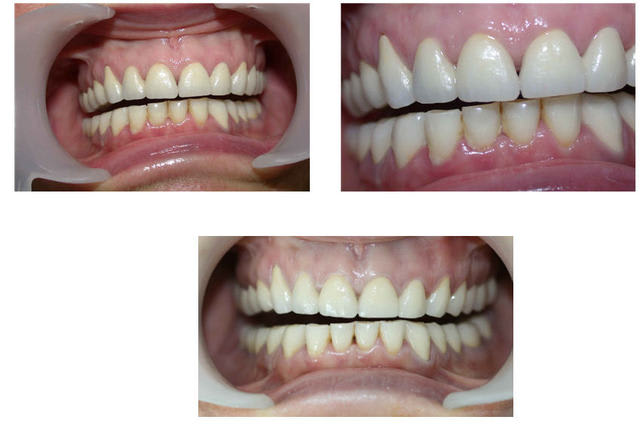

au passage en comparant photo initiale et celle ci après réalisation prothétique le recentrage des milieux est presque bien...

Je crois que sans le faire exprés, tu as présenté deux photos la 1 et la 2, dans le premier post qui semblent representer les latéralités gauche et droite.

comme on le voit la lateralité droite est facile et la gauche, beaucoup plus importante dans le désengrénement.

Ce qui fait penser aux AFMP de Planas et qui fait comprendre qu'une mastication préférentielle à droite depuis longtemps, a conduit à un dévellopement plus important du max sup droite qui explique le decentrage des points interincisifs.

pour reparler d'occluso au niveau de ce cas :

En utilisant le SAMII j'ai essayé(et je pense quand même y être un peu arrivé je m'expliquerai après) à faire travailler cette patiente en RC.

c'ESt le montage que nous avons réalisé dès le bridge provisoire, nous ne l'avons pas monté en PIM sur l'articu puis simplement augmenté la DV sur la tige incisive pour la réalisation provisoire.

mais j'ai transféré sur l'articu la patiente en RC pour qu'en fin on obtienne PIM en RC le plus possible.

ma remarque sur le recentrage des milieux n'était pas pour faire remarquer que c'est ce que nous recherchions mais plutôt d'observer qu'en modifiant Pim en RC on avait presque obtenu ce recentrage des milieux.

si on compare photo initale en occlusion la patiente est presque en articulé croisé alors qu'avec la photo du bridge conventionnel en occlusion on a vraiment une impression d'un réel recul mandibulaire que nous n'aurions pas obtenu en augmentant de façon simple la DV sur la tige incisive et c'est pour cette raison que je pense réellement que l'on a obtenu un fonctionnement en RC.